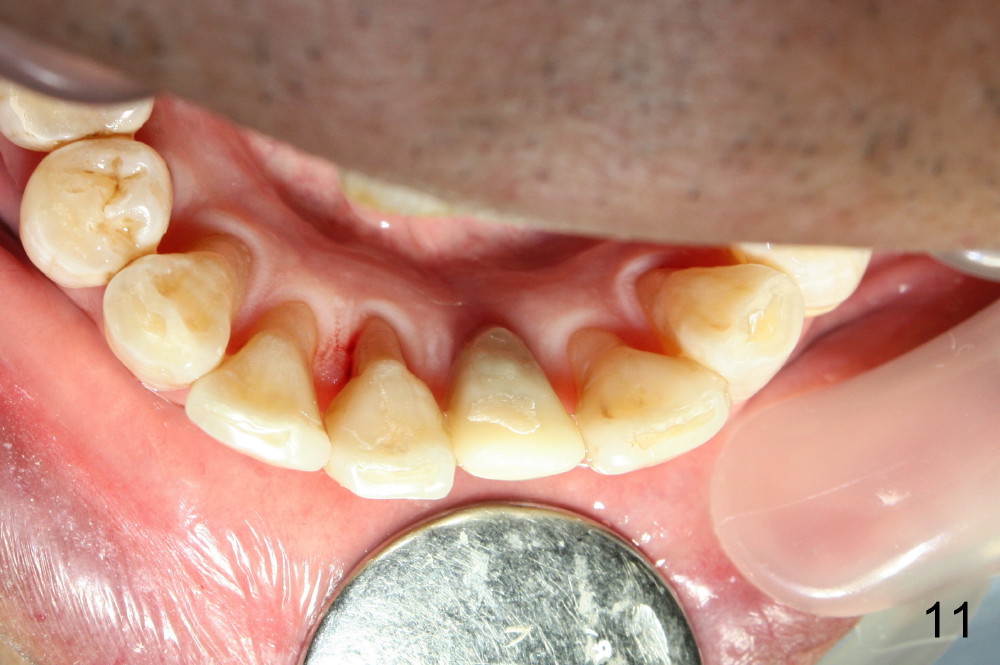

Fig.10,11 show 7 day follow up. The permanent crown is seated 4.5 months postop (Fig.12). Minimal bone resorption occurs at the crest 4 months postop (Fig.13), which is most likely associated with conservative approach (flapless). The patient returns for follow up 2.5 months post cementation (Fig.14,15). The implant remains in the bone 4 years post cementation (Fig.16 CT coronal section; lingual thread exposure, corresponding to preop defect in Fig.1). There is mild coronal bone resorption 5 years 4 months post cementation (Fig.17).